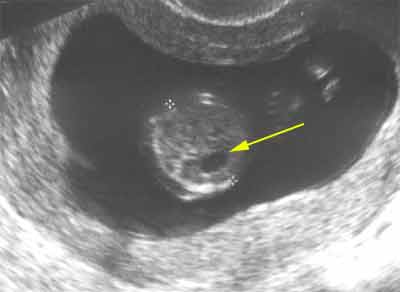

Estomac : Image anéchogène